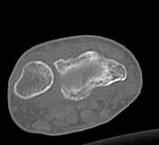

Уважаемые коллеги.Прошу обсудить случай лечения перелома дистального метаэпифиза лучевой кости. Ситуация скандальная и крайне неблагоприятная. Больная с патологической обстоятельностью мышления, склонностью к сутяжничеству, патологическими умозаключениями, не поддающимися коррекции (см. психиатрию, правда офиц. диагноза нет). В данном случае есть ряд ошибок с нашей стороны, прежде всего в отношении качества ведения документации (за что получил административное взыскание, по делом мне дураку). В остальном- придерживались в лечении подхода классический советской школы. Так как умную операцию…… сами знаете… 15.12- перелом луча в Москве. Там же репозиция, гипс. Дальнейшее лечение у нас в ЦРБ. 20.12.- вторичное смещение в гипсе21.12- под внутривенным наркозом- репозиция, гипсовая лонгета. Дальше начинается самое интересное. После репозиции больная заявила, что я (репозицию делал я) порвал ей все связки в суставе, посинел у нее 5 палец, якобы я за него тянул и т. д. На самом деле на 2 сутки после репозиции рука немного отекла и было незначительное сдавление гипсом, который был ослаблен. Дальнейшее лечение консервативное. Через 6 недель- гипс снят, назначено ЛФК. Пациентка крайне недовольна. Говорит, что на снимке у нее выступает кость, я ей сломал руку и.т.д. В общем началось. Пациентка прочитала в интернете наверное все, что есть по данной травме.По заключениями рентгенологов и консультанта из КДЦ областной больницы - стояние отломков допустимое. Объективно говоря- снижена высота лучевой кости, диастаз лучелоктевого сочленения, и не сросся шиловидный отросток. однако на РКТ при сравнении с другой стороной- разница незначительная. Дальше в одной из больниц нашей области и одной из больниц Москвы (вроде бы КГБ 53) врачи сказали, что репозиция сделана плохо. Нужна операция (восстановить длину лучевой кости), даже один из них предложил РЕДРЕССАЦИЮ (хи-хи) с наложением аппарата Илизарова. Что это для данной больной- радость неописанная. (см. описание психического статуса). Ничем другим, кроме зарабатывания дешевого авторитета объяснить данный факт не могу.Кстати, у больной еще нейропатия локтевого нерва.Для разрешения конфликта больная направлена на консультацию в ЦИТО на 03.03.11.

2. По сравнению и без ! втор смещение незначительное.НЕТ НИКАКОЙ ,,локтевой косорукости,,маделунгов . но имеется смещение совести у врачей КГБ 35--НЕТ ЗДОРОВЫХ, есть только недообследованные ! Этому смещению аппарат внешней фиксации не поможет .Психопаткам в менопаузе да весной только этого и надо чуть толкнули и поехало .

2.Укорочение лучевой кости и лучелоктевой диастаз невелики,но отрицать их клиническую значимость весьма сложно.

3.Исходя из конкретной ситуации и здравого смысла абсолютных показаний к операции не было и сразу после травмы и нет сейчас ,уже после сращения,поскольку перелом внесуставной,а осколок по тылу луча не препятствует торцевому упору по волярному краю луча.